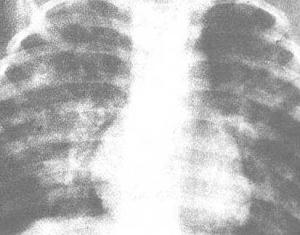

♥小儿慢性肺炎

小儿慢性肺炎病程超过3个月的小儿肺部炎症。近年来小儿急性肺炎病死率正在降低,但重症肺炎患儿有时未彻底恢复、复发及演变成慢性肺炎者颇不少见,慢性肺炎的特点是周期性的复发和恶化,呈波浪形经过。一旦发生,往往影响小儿的生长发育,因此,及时防治小儿慢性肺炎非常重要。